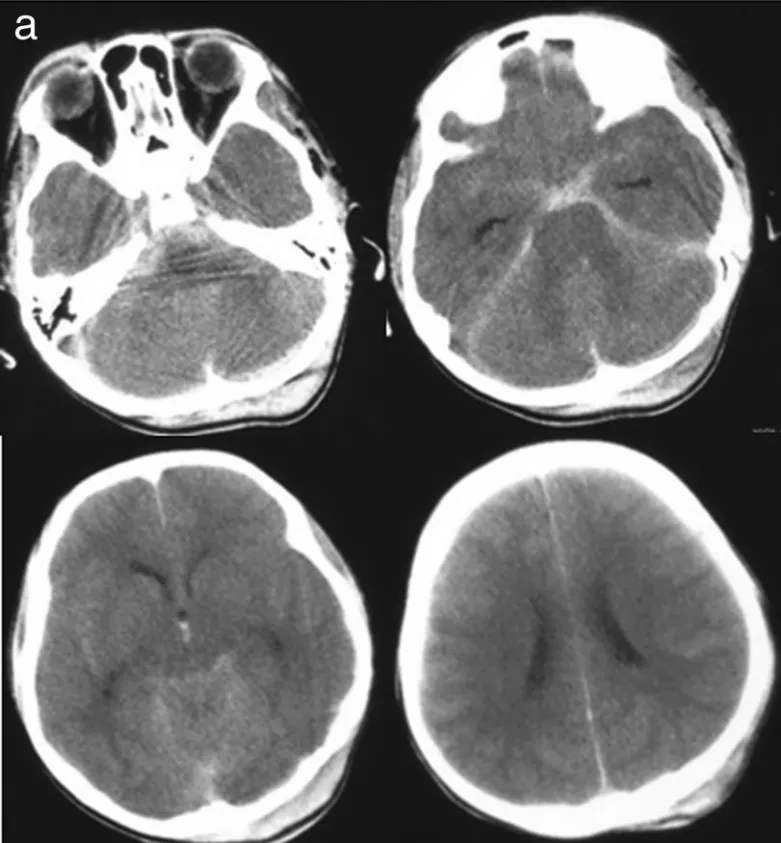

47岁男性患者陈先生在家中出现突发性剧烈头痛,随后迅速陷入昏迷状态。家属紧急送医后,急诊CT检查显示弥漫性蛛网膜下腔出血,左侧脑桥前池增厚表现明显。...